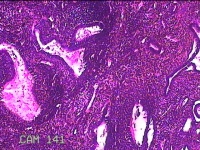

宫腔内容物

性别

女

年龄

48岁

临床诊断

宫腔占位

一般病史

发现宫腔占位1天。

标本名称

大体所见

灰白暗红色肿物2.2x1.3x0.2cm一个,表面糜烂,切开肿物呈实性,切面灰白暗红色,质软。